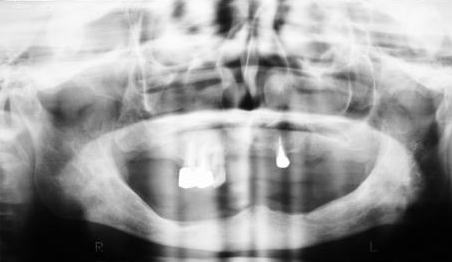

(図3)初診から2年後(1977年7月)、40歳。Splintせずに機能している